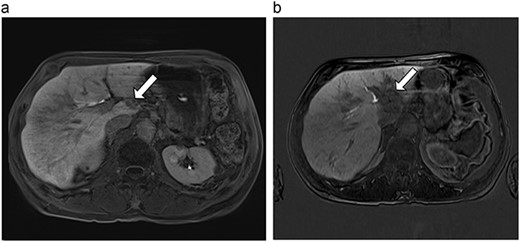

(a) Pre-ablation MRI demonstrating 5 mm lesion in caudate lobe of liver. (b) Post-ablation MRI (19 days postoperatively) demonstrating 36.2 mm complete ablation of caudate lesion.

| 3 (5a,b) | 68, F | Colon adenocarcinoma | 6 cycles modified FOLFOX-6 | 8 | Laparoscopic microwave ablation and low anterior resection of colon | 5 | 36.2 | 31.2 | 15 | No |